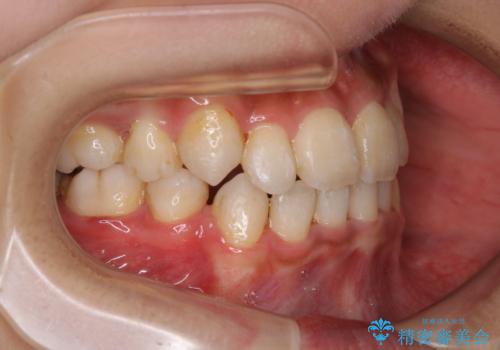

- 元々は海外でワイヤー矯正を行っていたが、コロナ禍で海外への往来が難しくなり、治療を中断せざるを得なくなってしまった方です。

ご本人のご希望により、インビザラインによる治療を行いました。

ブラケット除去直後に目立っていた下顎前歯部の大きなブラックトライアングルもあまり目立たなくなり、大変喜んでいただけました。